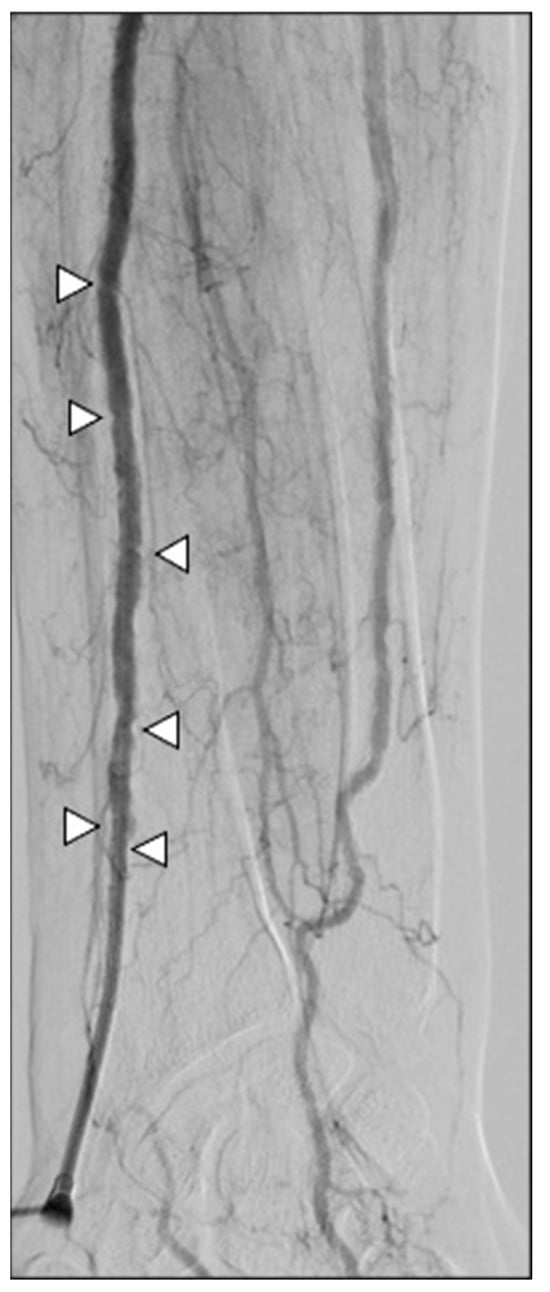

2.4. Procedures